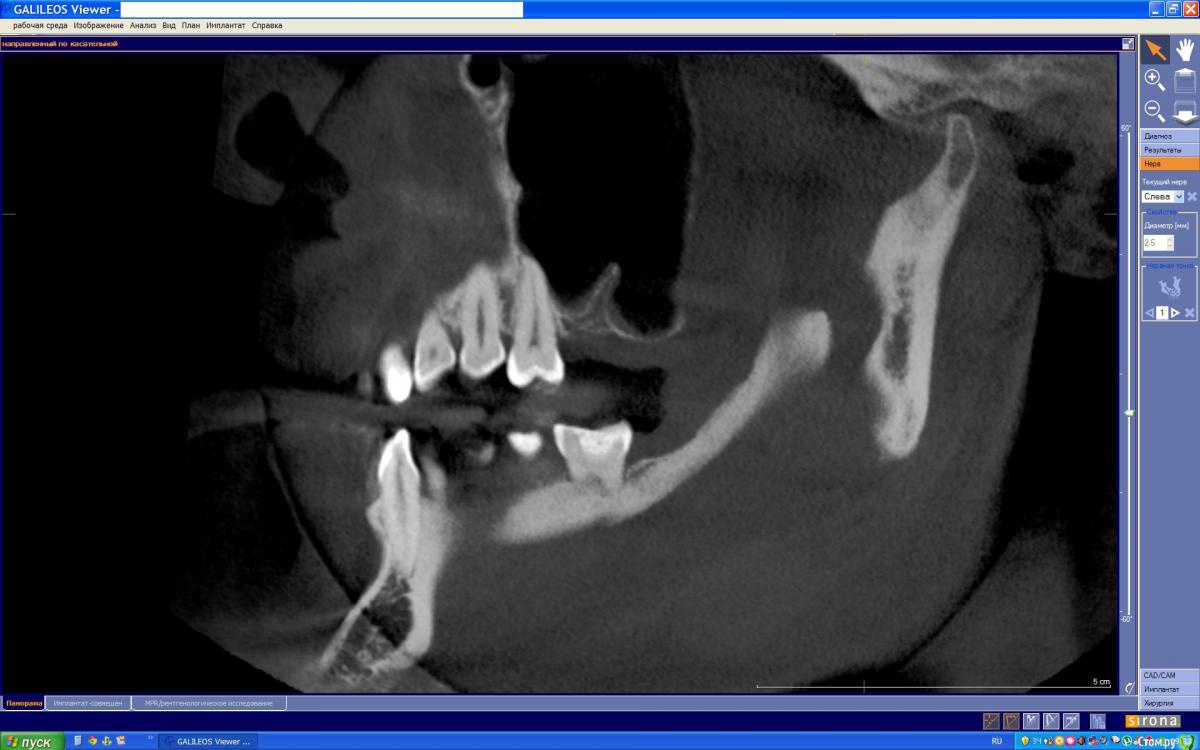

Azara Опубликовано 7 июня, 2015 Поделиться Опубликовано 7 июня, 2015 Здравствуйте, уважаемые специалисты. На консультации хирург-имплантолог изучив снимки КТ сказал, что случай сложный и из-за строения практически отсутствующей кости верхней челюсти нужно заполнять 2 полости, для чего потребуется сделать 2 окна в кости через которые будут проводится 2 операции по заполнению, и возможно что через год потребуется повторное заполнение. Ввиду физиологического строения, нехватку данного зуба я довольно остро ощущаю. Но к сожалению я морально не готова перенести такое добровольное "издевательство" над своим организмом. Врач сказал что на раздумья у меня полгода. Есть ли какая то другая возможность по восстановлению данного зуба без имплантации? Если все же только имплантация то другой способ синус-лифтинга? Зуб удален год назад. Заранее спасибо за ваше мнение. Ссылка на папку со снимками КТ https://yadi.sk/d/OksbhWPth8JVw И скриншоты с КТ Ссылка на комментарий